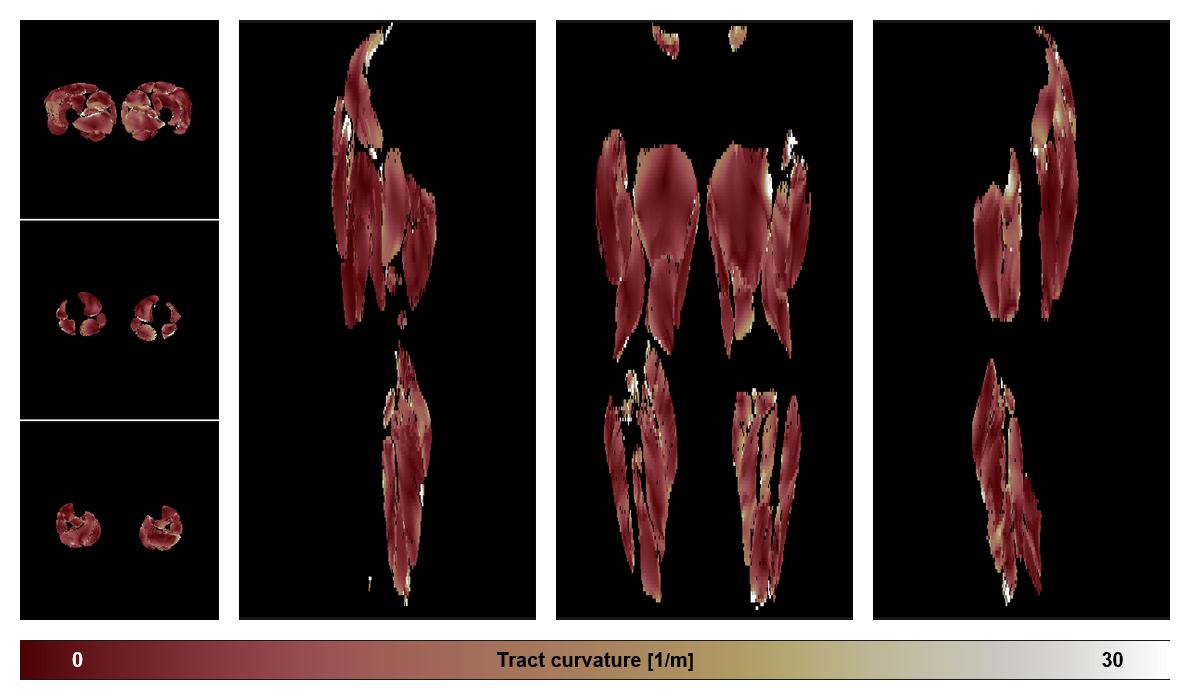

• Muscle fiber curvature map

Muscle fiber tract curvature map based on whole leg DTI based fiber tractography.